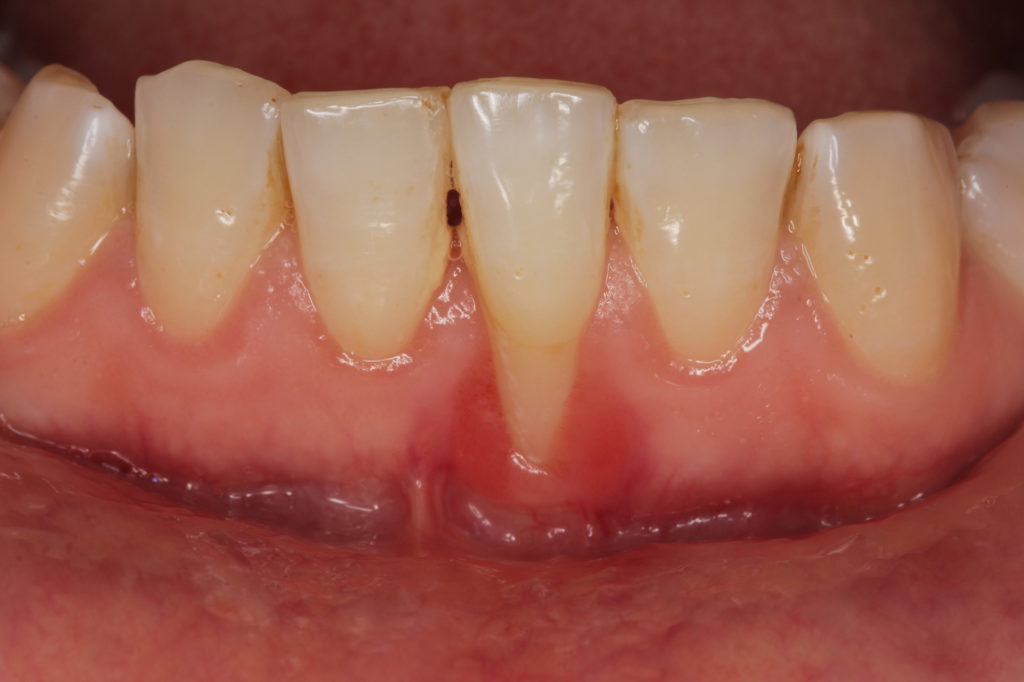

Receding gums can be limited to a single tooth or several teeth and may induce signs and symptoms such as:

- Root Exposure

- Tissue Inflammation

Receding gums are among the most noticeable side effects of periodontal disease. This condition can be limited to a single tooth or affect many teeth, and symptoms may include root sensitivity, gum tissue inflammation, and aesthetic concerns, among others. Receding gums need to be addressed as soon as possible because the gums serve as a shield to bacteria. If you do not have enough gum tissue around the teeth, you may be at a higher risk for developing gum disease or even suffering tooth loss.

Many people with receding gums are self-conscious about how their teeth appear to be larger than average or if there is a lot of tooth surface showing when they smile. When gum disease has caused loss of supporting tooth structures, a gum grafting procedure can restore the gum line and improve overall oral health.